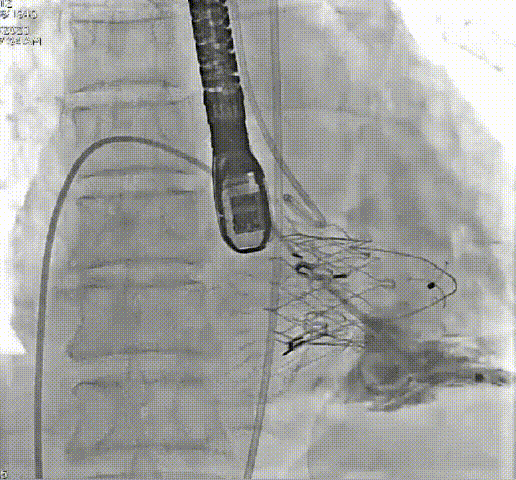

术前、术后造影结果

三例患者均在全身麻醉下穿刺右侧颈静脉建立手术入路,在X线及超声引导下,将输送系统送到右心房,通过调整弯度,顺利跨过三尖瓣口进入右心室,释放夹持件,使其固定在三尖瓣前瓣,再通过藏针将锚定件固定在室间隔,最后撤出输送系统,完成LuX-Valve Plus人工三尖瓣瓣膜的植入。

演示视频LuX-Valve经导管三尖瓣置换系统在国际上率先采用“非径向支撑力”和“室间隔固定”设计理念,可更好适应三尖瓣结构,减少并发症,是我国拥有完全自主知识产权的心脏瓣膜介入器械。LuX-Valve Plus是LuX-Valve第二代产品,采用经颈静脉入路,可通过穿刺建立入路,实现完全介入治疗,进一步减小损伤。